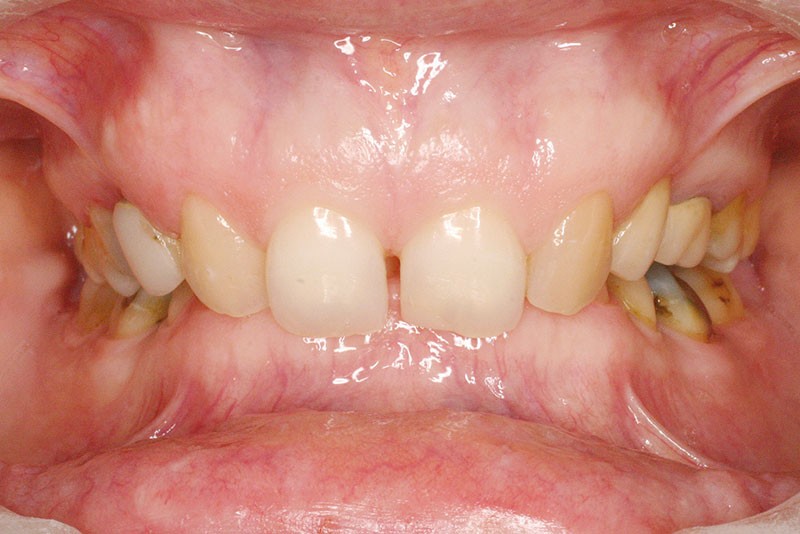

La patiente, âgée de 30 ans, présente des agénésies multiples : 12, 22, 14, 15, 24, 25, 35 et 45 (fig. 1 à 3).

Malocclusion de classe II par rétrognathie mandibulaire dans un schéma squelettique hypodivergent (fig. 4 à 6).

On note une forte supraclusion incisive (fig. 7 à 9).

Un traitement orthodontique a déjà été effectué pendant son adolescence avec un choix de fermeture d’espaces qui a entraîné une linguoversion incisive maxillaire excessive (fig. 10), avec un préjudice esthétique important notamment sur le sourire (fig. 11 à 13).